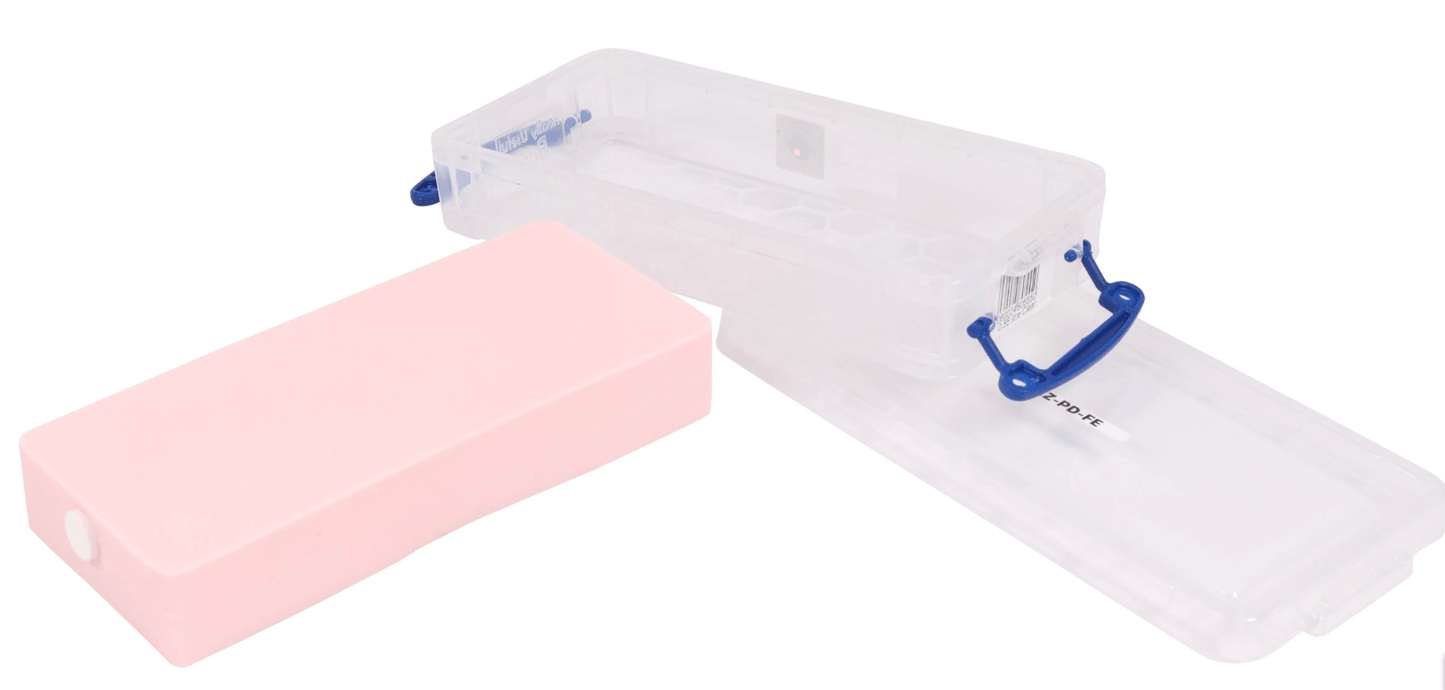

Der SonoEZ Pädiatrische Ultraschalltrainer „Femur“ ist ein hochentwickeltes Trainingsmodell, das die Femoralgegend bei einem pädiatrischen Patienten realistisch darstellt. Das Modell enthält zwei wichtige Gefäße: die Femoralarterie und die Femoralvene, die mit Flüssigkeit gefüllt sind. Durch Druck auf die Sonde wird die Femoralvene komprimiert, was eine realistische Simulation für die Ultraschalluntersuchung und Kanülierung bietet. Das Modell ist zudem katheterisierbar, was eine praxisorientierte Übung für medizinisches Fachpersonal ermöglicht. Ideal für die Ausbildung und das Training in der Ultraschalldiagnostik und Katheterisierung.

Der SonoEZ Pädiatrische Ultraschalltrainer „Femur“ bietet eine präzise Simulation der Femoralgegend und ermöglicht das Üben von Ultraschalluntersuchungen sowie Katheterisierungen. Es ist ein wertvolles Trainingsinstrument für die Ausbildung in der pädiatrischen Sonographie und der Behandlung von Gefäßen.

Lagerung:

Lagern Sie das Modell an einem trockenen, kühlen Ort, um seine Lebensdauer und Bildqualität zu erhalten.